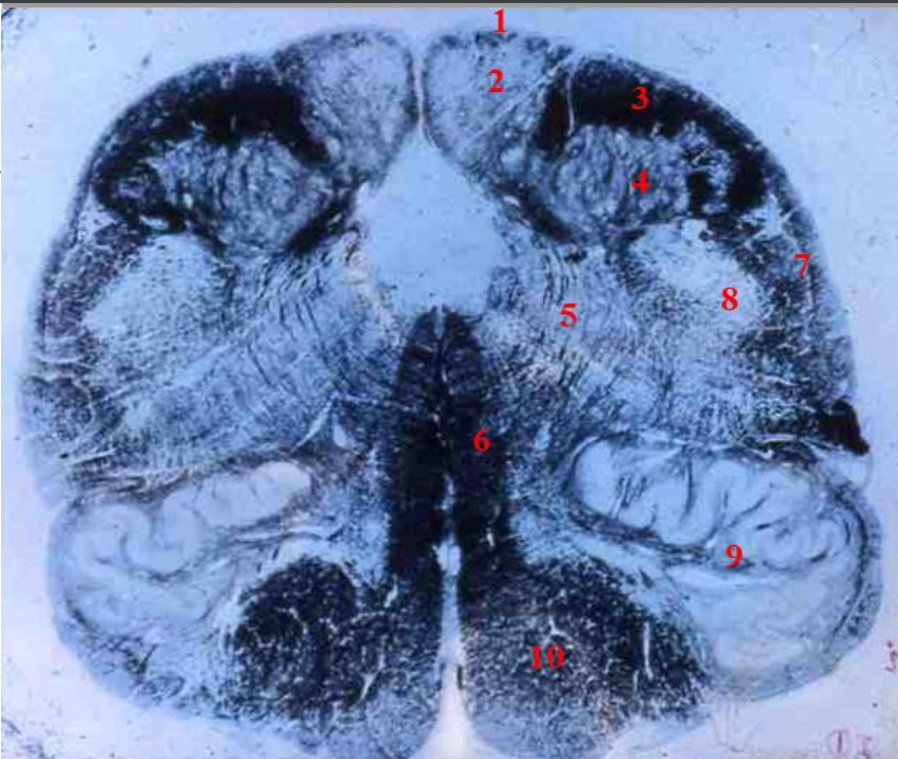

identify the weigert

upper medulla

1

fourth ventricle

29

2

hypoglossal nucleus

30

3

dorsal motor nucleus of CN X - vagus

31

4

vestibular nuclei

32

5

solitary tract (black)

33

6

medial lemniscus

34

7

inferior olivary nucleus (only seen on upper medulla)

35

8

olivocerebellar fibres crossing to the inferior cerebellar peduncle

36

9

inferior cerebellar peduncle

37

10

pyramid